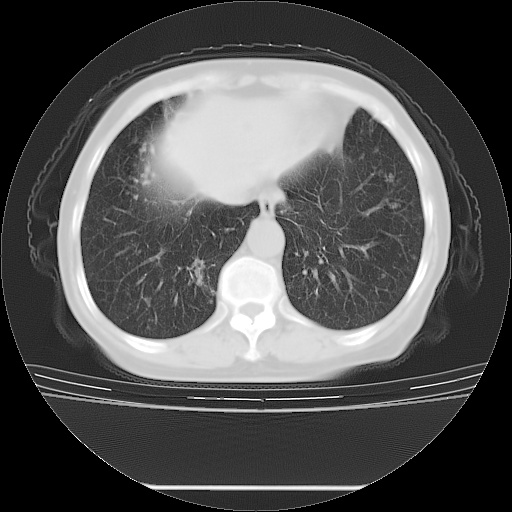

患者女性,72岁,慢性咳嗽3月余,曾抗炎治疗无效果,最近抗结核治疗约半月余,症状缓解。

ct示两肺粟粒状病灶,以两肺上叶尖后段及下叶背段分布为主;首先考虑结核。请战友们分析。

考虑 1 弥漫性泛细支气管炎, 2 结核不除外/.  有小叶中心结节 和 树芽征!!

两肺内病灶呈小结节状和树芽状,纵膈的肿大的淋巴结密度不均匀,并见有钙化,考虑为两肺结核可能更大些。

两肺内病灶呈小结节状和树芽状,纵膈的肿大的淋巴结密度不均匀,并见有钙化,多形态病灶,考虑为两肺结核,肝内考虑小囊肿。

病灶以结节为主,大部分边界清楚,分布不均,病灶形态较单一,偶见空泡征,纵膈淋巴结肿大钙化,无结核中毒症状考虑 感染性病变【真菌类可能性大】,细支气管肺泡癌。其他待排

片子很好,质量很高,两侧肺门淋巴结肿大并有钙化,两肺弥漫病灶,首先考虑tb并播散,但年龄大了呀(72岁)小细胞肺癌不能除外,如果是肺癌也没什么大的治疗了,建议正规抗结核治疗后复查